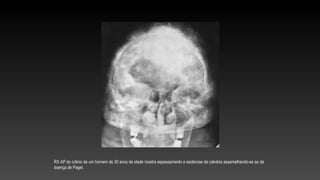

RX AP do crânio de um homem de 30 anos de idade mostra espessamento e esclerose da calvária assemelhando-se ao da

doença de Paget.

Estudo com ampliação revela acentuado espessamento da tábua interna e alargamento da díploe.